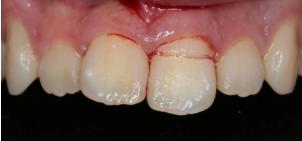

“旧冠再利用”术前牙冠大面积折断,露牙髓:

折断的牙冠:

根管治疗术前、术后:

根管治疗后牙冠重新粘接: